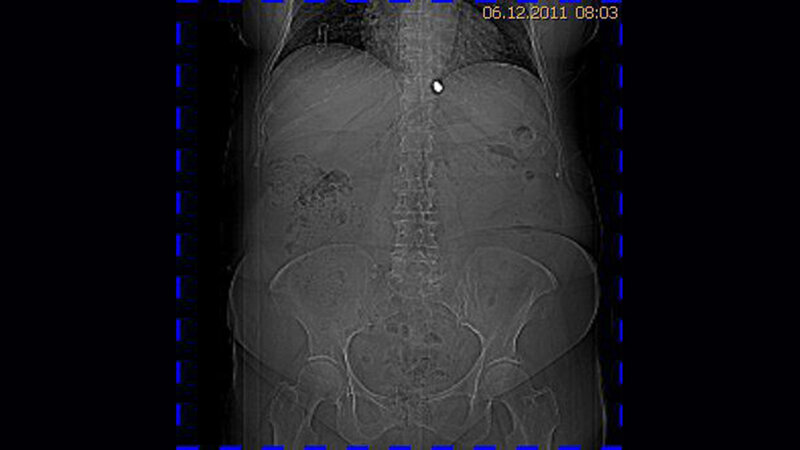

Zufallsbefunde: Schussverletzung (Lungensteckschuss)

Metallartefakte werden in der Computer- oder Kernspintomographie häufig gefunden. Dabei kann es sich um operativ bedingte Clips an kleinen Gefäßstrukturen handeln, um Teile von Gefäßprothesen oder auch um Gelenkprothesen.

Die Radiologen können bei Patienten mit Schussverletzungen Diagnostik und Behandlung sichern. Die Röntgenaufnahmen, CT, Angiographie und MRT lokalisieren das Projektil und den Schusskanal,

stellen Begleitverletzungen fest, Knochen- und Projektilfragmente.